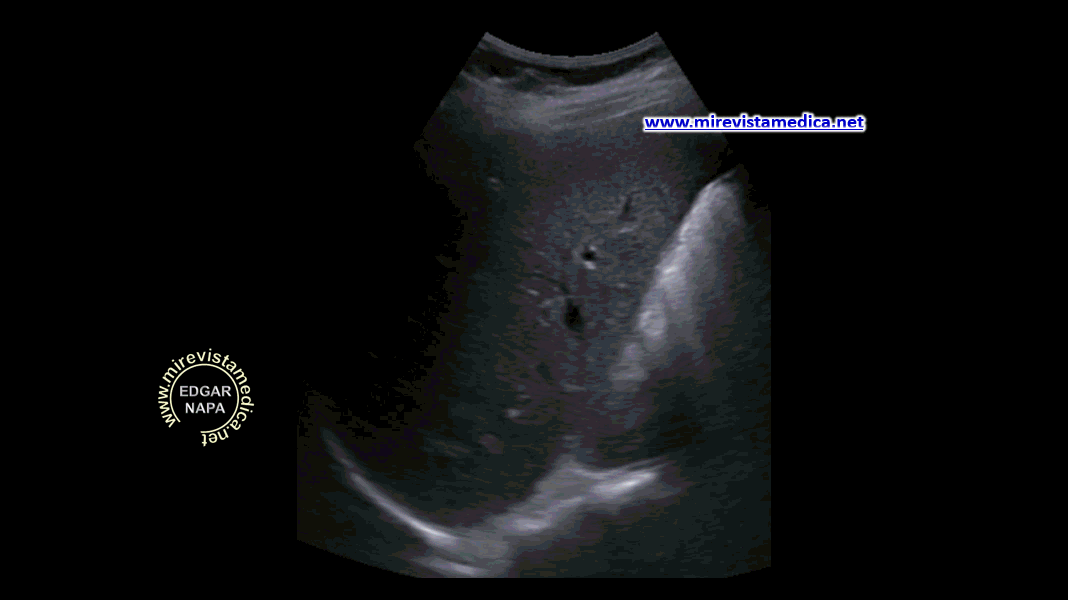

El parénquima pancreático presenta ecos finos distribuidos de manera homogénea, no evidenciándose lesiones focales,

Los contornos de la silueta pancreáticas son circunscritos, liso (en algunas ocasiones lobulado).

En la imagen ecográfica,

vista transversa, se observa parcialmente la silueta pancreática, no se observa la cola, por interposición de asas intestinales.